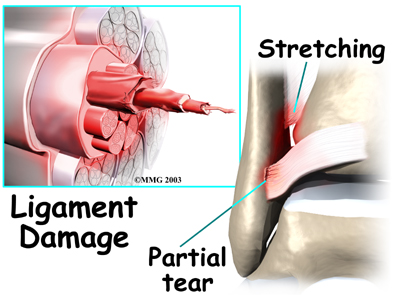

An ankle syndesmosis injury involves a sprain of one or more of the ligaments that support the ankle syndesmosis. A ligament is made up of multiple strands of connective tissue, similar to a nylon rope. A sprain stretches or tears the ligaments. Minor sprains only stretch the ligament. A tear may be either a complete tear of all the strands of the ligament or a partial tear of only some of the strands. The ligament is weakened by the injury. How much it is weakened depends on the degree of the sprain.

Multiple Strands of Connective Issue

Partial Tear